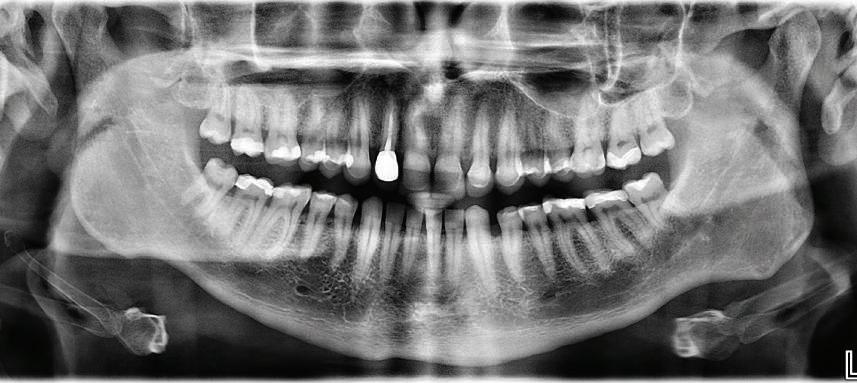

20 Dental Tribune Bulgarian Edition / октомври 2022 г. П ациентите със завършен растеж и скелетни проблеми обикновено представляват предизвикателство за ортодонт ската практика. Необходимостта от изваждане на зъби в комбинация с особеностите на възрастовата ортодонтия изисква особено внима ние. Фокусът върху критично важното значение на позицията на долните резци във връзка с дългосроч ната стабилност и постигането на оптимални оклузални взаимоотношения при затварянето на екстракционните пространства лесно може да излезе извън контрол. Когато към тези чисто кли нични проблеми се добави и стресът от натоваре ната практика, предизвикателството става още по-голямо. Всички тези фактори налагат използ ването на доказан подход с ясни и последовател ни стъпки, в което се разкрива силата на дисциплината „Алекзандър“ – предвидим протокол през целия процес на елиминиране на ротациите, ниве лиране на дъгите, затваряне на екстракционните пространства и финализиране на случая. Именно такъв е и случаят, който презентираме –екстракционен, скелетен клас 3 при възрастен па циент, лекуван по системата „Алекзандър“. ПРЕДВИДИМИ РЕЗУЛТАТИ ПРИ ПАЦИЕНТИ СЪС ЗАВЪРШЕН РАСТЕЖ И СКЕЛЕТЕН КЛАС 3, ИЗПОЛЗВАЙКИ ЕКСТРАКЦИОННО ЛЕЧЕНИЕ ПО ДИСЦИПЛИНАТА „АЛЕКЗАНДЪР“ Д-р Радой Димитров, България Преди започване на лечение клиничен случай | ортодонтия Фиг. 1а–1e Преди започване на лечение. Пациентът пристига в практиката с основното оплакване от невъзмож ност за нормално дъвчене. Снета е цялата необходима диагностична ин формация. Фиг. 1f–1h Снимки в профил и анфас. Фиг. 1i–1k Панорамна снимка, телерентгенография и анализ на телерент генография. Фиг. 1а Фиг. 1d Фиг. 1f Фиг. 1g Фиг. 1h Фиг. 1e Фиг. 1b Фиг. 1c Фиг. 1i Фиг. 1j Фиг. 1k

closed.

21Dental Tribune Bulgarian Edition / октомври 2022 г. ДИАГНОСТИЧНИ РЕЗУЛТАТИ: 1. Възраст на пациента: 21 години 2. Скелетен клас III (ANB 0) 3. Зъбен клас 3 4. Ръбцова захапка във фронта, кръстосана в дисталните участъци 5. Тясна горна челюст 6. Overjet – 0 мм, Overbite – 0 мм 7. Несъответствие на горната с долната средна линия 8. Единични контакти в ЦО 9. Хиподивергентен тип на растеж SN/MP – 33.5 10. Неравен гингивален контур 11. Неравна линия на усмивката 12. Тенденция за рецесии в долен фронт ПРЕПОРЪЧИТЕЛНО ЛЕЧЕНИЕ: Пълно ортодонтско лечение с метални брекети „Алекзандър“ Корекция на клас 3 захапката в областта на кучешките зъби с екстракция на първите пре молари в долна челюст Корекция на кръстосаната захапка в дистални участъци Коригиране на ръбцовата захапка във фронта Подобряване на ОJ и OB на пациента Стрипинг в долен фронт Подреждане на зъбите в горната и долната челюст Професионално хигиенизиране и профилактични дентални прегледи са препоръчителни на всеки 6 месеца. 1-ви месец След 1 месец са залепени брекети в горната челюст – поставена е еластична дъга. 016 NiTi. В долната челюст са елиминирани ротациите, поставена е стоманена дъга. 016SS, закалена с ток, и еластична верижка за затваряне на пространствата. 3-ти месец В долната челюст е поставена трета дъга – 17 x 25 NiTi с къси лигатури и верижка

В горната челюст се затварят пространствата с дъга .016SS и верижка. 5-и месец На 5-ия месец след залепяне на брекетите в долната челюст е поставена стоманена дъга 16 x 22 SS с четвъртито сечение, омега луп и тай бек. В горната челюст е поставена дъга 17 x 25 NiTi. Поради липсата на стабилни оклузални контакти са поставени лингвални верижки в областта на моларите, за да се предотврати нежелана ротация на 7-ите зъби. 6-и месец На 6-ия месец от началото на лечението са екстрахирани долните първи премолари, поставена е дъга 16 x 22 SS със затваряща чупка teardrop. Чупката се активира всеки месец по 1 мм с чинч-бек. клиничен случай | ортодонтия СТЪПКИ НА ЛЕЧЕНИЕТО Начало на лечението Лечението започва с поставяне на апарат за бърза експанзия в горната челюст. През първия месец от лечението са направени 24 оборота на апарата за експанзия. Залепени са брекети в долната челюст, поставена е дъга 17x25 CuNiTi, като са предпи сани клас 3 ластици (1/4”,4 1/2 oz) по време на сън, за да се осигури контрол върху торка на долните резци. Фиг. 2а Фиг. 3a Фиг. 4a Фиг. 3b Фиг. 4b Фиг. 3c Фиг. 4c Фиг. 3d Фиг. 4d Фиг. 3e Фиг. 4e Фиг. 5a Фиг. 5b Фиг. 5c Фиг. 5d Фиг. 5e Фиг. 6a Фиг. 6b Фиг. 6c Фиг. 6d Фиг. 6e Фиг. 7a Фиг. 7b Фиг. 7c Фиг. 7d Фиг. 7e Фиг. 2b Фиг. 2c Фиг. 2d

Dental Tribune Bulgarian Edition / октомври 2022 г.22 клиничен случай | ортодонтия 14-и месец В горната и долната челюст са поставени последни стоманени дъга с омега луп и тай бек – 17 x 25 SS с четвъртито сечение. Назначени е ластик за средната линия в комбинация с клас 3 ластик (1/4”, 6 1/2 oz). Контролни рентгенографии 13-и месец Екстракционните пространства са затворени. Направена е контролна панорамна снимка за оценка позицията на корените. Взето е решение за презалепване на брекетите на 12, 22 и пръстените на 36 и 46. 21-ви месец Средната линия в горната и долната челюст съвпадат. Ластиците са спрени. Свалени са пръстените и брекетите в горната и долната челюст, зигзаг ластици не са използвани поради благоприятните оклузални взаимоотношения. Фиг. 11j Ортопантомография в края на лечението. Фиг. 11k Телерентгенография след края на лечението. Фиг. 11l Анализ на телерентгенографията след лечението. Фиг. 11m Последователност на дъгите в горната и долната челюст Фиг. 11n Суперимпозиция на PreOp и PostOp ортопантомографии. 10-и месец Затварянето на пространствата е предвидимо и контролирано, без да се отварят пространства в зъбната дъга. Фиг. 8a Фиг. 8b Фиг. 8c Фиг. 8d Фиг. 8e Фиг. 10a Фиг. 10b Фиг. 10c Фиг. 10d Фиг. 10e Фиг. 9a Фиг. 9b Фиг. 9c Фиг. 9d Фиг. 9e Фиг. 9f Фиг. 11a Фиг. 11f Фиг. 11j Фиг. 11l Фиг. 11m Фиг. 11n Фиг. 11k Фиг. 11g Фиг. 11h Фиг. 11i Фиг. 11b Фиг. 11c Фиг. 11d Фиг. 11e

Dental Tribune Bulgarian Edition / октомври 2022 г. 23клиничен случай | ортодонтия реклама Лечението е продължило 21 месеца. Проведено е домашно избелване с индивидуални шини. За автора: Д-р Радой Димитров завършва с отличие Факултета по дентална медицина към МУ–София през 2015 г. В продължение на 5 години работи в няколко водещи практики в София, като през 2019 г. заедно със своята съпру га д-р Траяна Димитрова основават собствена практика в гр. Гоце Делчев –Dimitrovi Dental Care. Посещава редица курсове за повишаване на квалификаци ята, но най-сериозен тласък в развитието на ортодонтската си практика получава след завършването на комплексната ортодонтска програма, воде на от д-р Иван Горялов, базирана на дисциплината „Алекзандър“ – система с повече от 50 години опит в целия свят. Д-р Димитров е член на Българския изследователски клуб „Алекзандър“. Взе ма участие като гост-лектор в симпозиума с международно участие The Power of the Alexander Discipline, който се проведе на 14–15.05.2022 г. С д-р Ди митров можете да свържете на тел. +359885 252 025. Заключение Представеният случай е ярък пример за възможностите и красо тата на дисциплината „Алекзандър“ – приложен е утвърден под ход с ясни правила и са постигнати очакваните цели. Резулта тът ще бъде дългосрочно стабилен, тъй като са спазени всички правила, които се отнасят към максимално комфортната пози ция на зъбите в края на лечението. Постигнати са красива усмив ка и стабилна оклузия. ПОСТИГНАТИ РЕЗУЛТАТИ ОТ ЛЕЧЕНИЕТО 1. Коригирана ръбцова захапка 2. Коригирана клас 3 захапка в областта на ку чешките зъби 3. Коригирана кръстосана захапка в дисталните участъци 4. Коригиран овърджет и овърбайт 5. Разширена е горната зъбна дъга 6. Подредени зъби в горната и долната челюст 7. Постигната е стабилна захапка с множество контакти в ЦО 8. Драматично е подобрена дъвкателната функ ция 9. Подобрена е линията на усмивката ДРУГИ ПРОВЕДЕНИ ДЕНТАЛНИ ПРОЦЕДУРИ 1. Домашно избелване на зъбите 2. Екстракция на мъдреците Фиг. 12a Фиг. 12b Фиг. 12c Фиг. 12eФиг. 12d Фиг. 12f Фиг. 12g Информация за дати, цени и отстъпки www.bracescourses.com 0889 22 55 01 Практически курсове лектор д-р Иван Горялов Дисциплината „Алекзандър“ ПЪТЯТ КЪМ СУПЕРУСМИВКИТЕ 100% връщане на цялата сума, ако не сте удовлетворени след преминаване на Ниво 1 Директно и индиректно залепяне на брекети Анализ, диагноза и план на лечение Лечение на клас 2 дълбока захапка Екстракционно лечение Лечение на клас 3 отворена захапка НИВО 5НИВО 1 НИВО 2 НИВО 3 НИВО 4